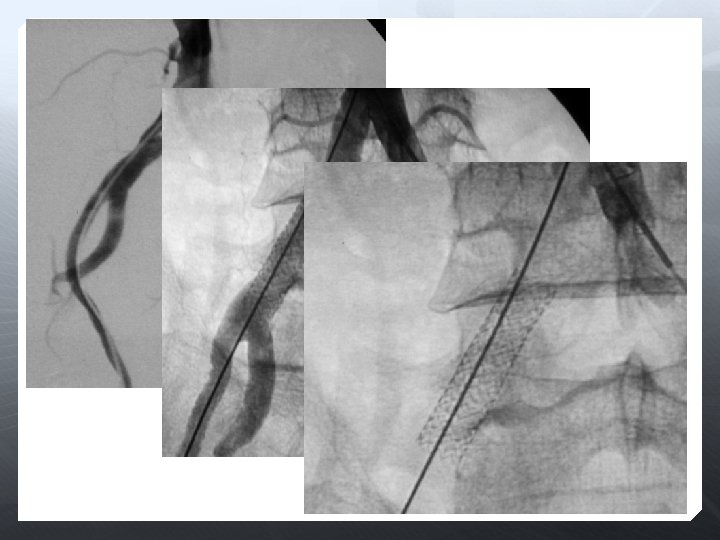

Darlık Oklüzyon Aorto-iliak Femoral-popliteal Infrapopliteal

SFA

Re-entry cihazı